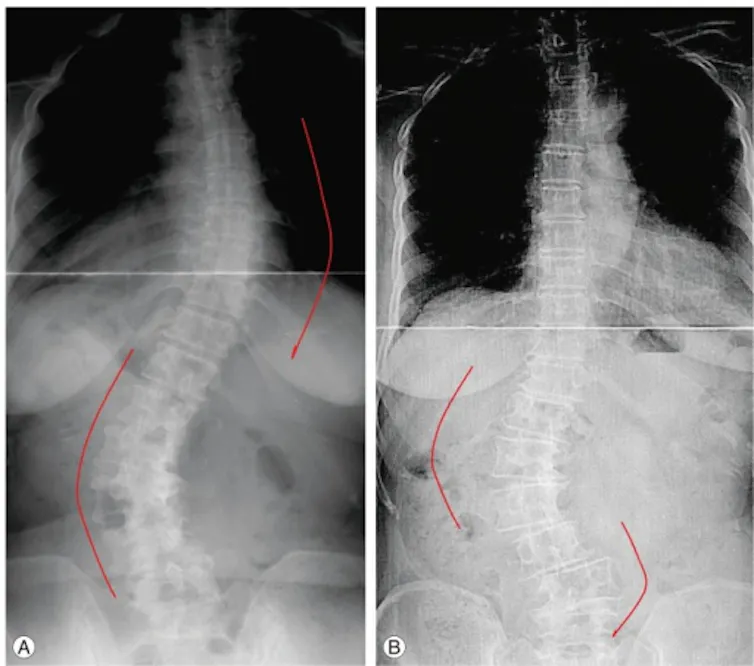

(Cho KJ, Kim YT, Shin SH, Suk SI), CC BY-NC

The recommended care in North America involves bracing for mild to moderate curves (25° to 45°) and surgery for curves exceeding 45°. Shockingly, 32 per cent of Canadian children, like Cael, face delayed referrals, discovering significant curves when they finally see specialists.